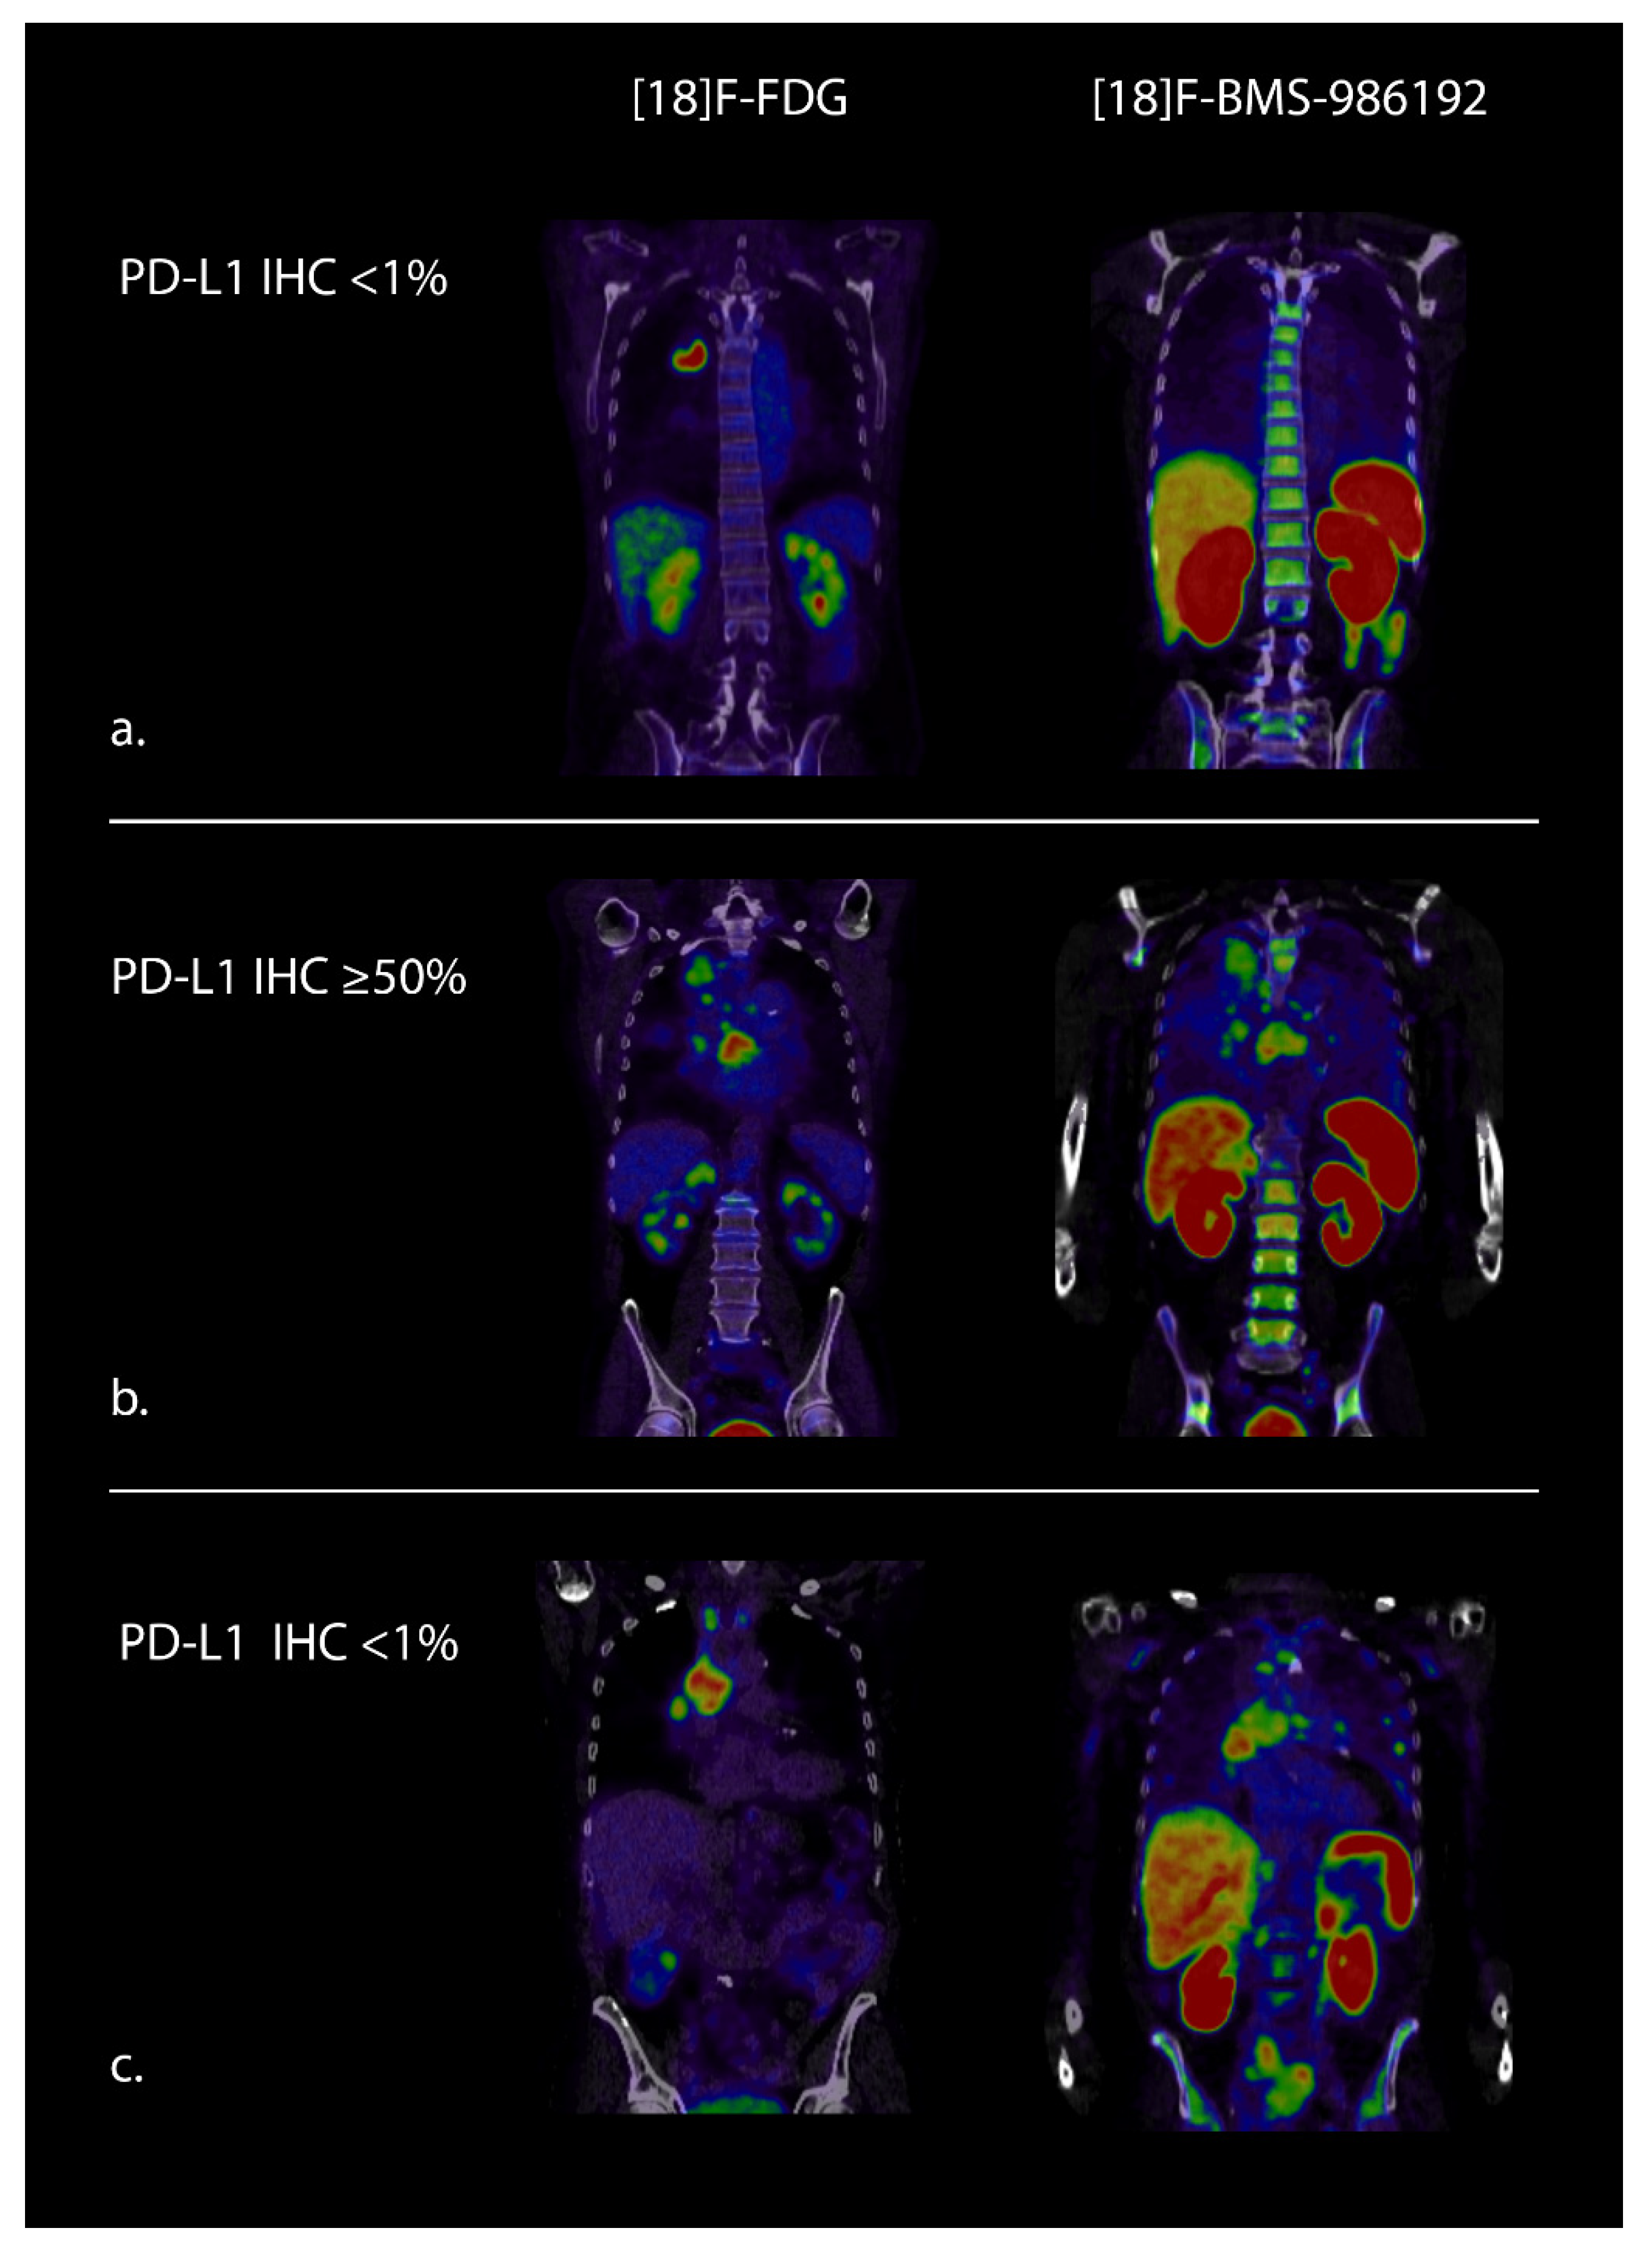

- Niemeijer, A.N.; Leung, D.; Huisman, M.C.; Bahce, I.; Hoekstra, O.S.; Van Dongen, G.A.M.S.; Boellaard, R.; Du, S.; Hayes, W.; Smith, R.; et al. Whole body PD-1 and PD-L1 positron emission tomography in patients with non-small-cell lung cancer. Nat. Commun. 2018, 9, 1–5. [Google Scholar] [CrossRef]

- Stutvoet, T.S.; van der Veen, E.L.; Kol, A.; Antunes, I.F.; de Vries, E.F.; Hospers, G.A.; de Vries, E.G.E.; de Jong, S.; Lub-de Hooge, M.N. Molecular imaging of Pd-L1 expression and dynamics with the adnectin-based pet tracer (18)F-Bms-986192. J. Nucl Med. 2020, 61, 1839–1844. [Google Scholar] [CrossRef]